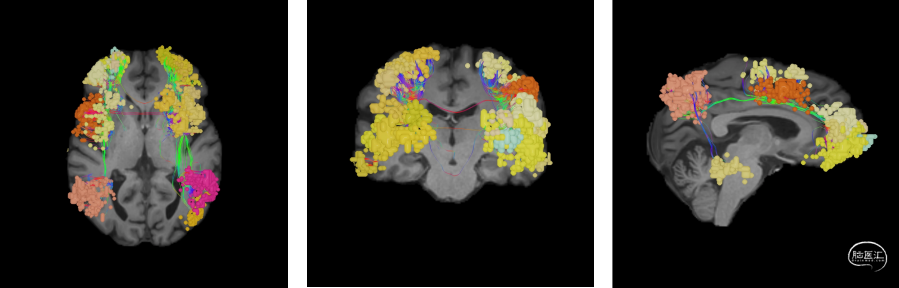

术前采用Nura Surgical脑网络重建分析

使用解剖像磁共振数据+DTI成像,基于Nura Surgical的独特算法追踪全脑的白质纤维束,并使用技术进行个体化的大脑重新分区,生成关键大脑结构网络。根据肿瘤与关键白质纤维束及功能网络的关系,确定收到肿瘤影响最为严重的大脑结构网络为中央执行网络,受到肿瘤影响最为严重的关键关键白质纤维束为皮质脊髓束。其中,中央执行网络的额叶部分与肿瘤关系密切,分布在肿瘤的外下方,应考虑在手术中进行保护。皮质脊髓束没有受到肿瘤直接影响,但受到肿瘤引起的水肿导致患者皮质脊髓束明显被推挤向后移位,预估术后可部分恢复,对患者运动功能影响不大。

图1:正常中央执行网络的脑网络结构(左图:轴位;中图:冠状位;右图:矢状位)

(备注:中央执行网络络是大脑最主要的网络之一,主要是负责任务执行、决策和目标规划等高级认知功能,损伤中央执行网络,可能会带来抑郁、言语失利、工作记忆障碍、导航障碍、妄想、幻觉、注意障碍、记忆检索困难等神经功能障碍)